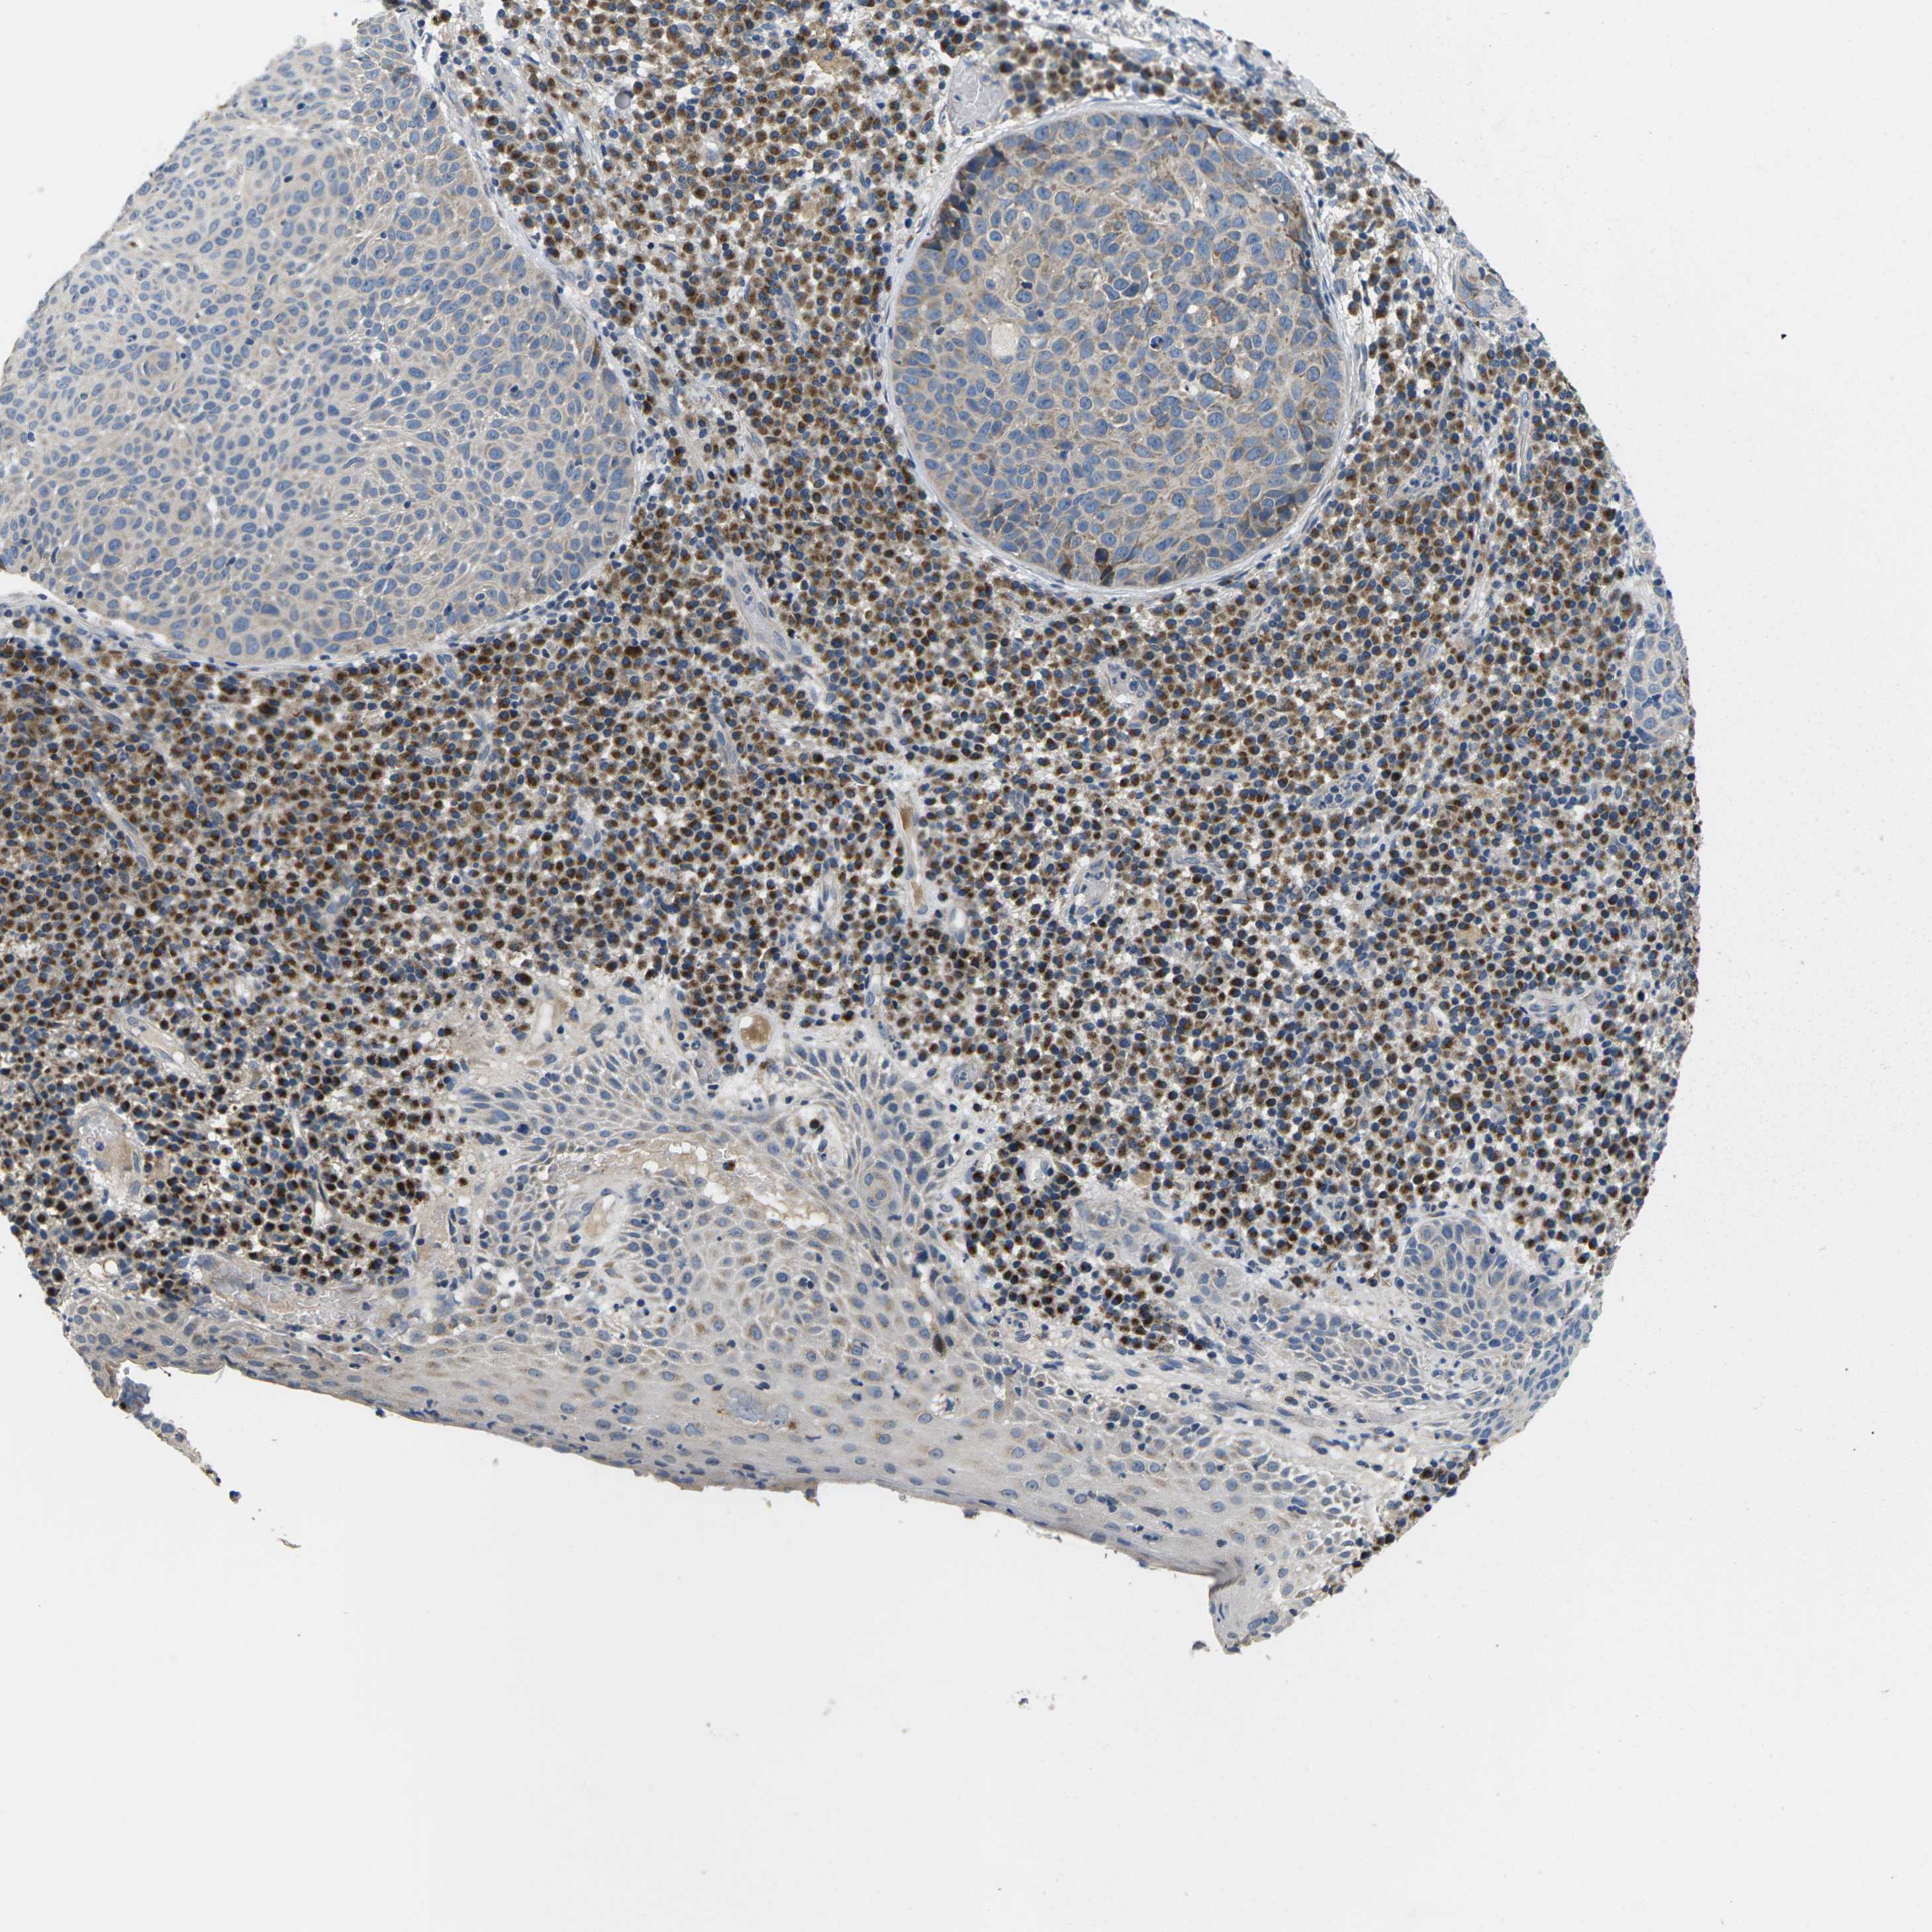

SKIN CANCER - Protein expressioni

A mouse-over function shows sample information and annotation data. Click on an image to view it in a full screen mode. Samples can be filtered based on level of antibody staining by selecting one or several of the following categories: high, medium, low and not detected. The assay and annotation is described here.

Antibody stainingi

Antibody staining in the annotated cell types in the current human tissue is reported as not detected, low, medium, or high, based on conventional immunohistochemistry profiling in selected tissues. This score is based on the combination of the staining intensity and fraction of stained cells.

Each image is clickable and will lead to virtual microscopy that enables deeper exploration of all samples and also displays staining intensity scores, fraction scores and subcellular localization as well as patient and tissue information for each sample.

Antibody HPA015242

Antibody HPA015968

Staining

High

Medium

Low

Not detected

Intensity

Strong

Moderate

Weak

Negative

Quantity

>75%

75%-25%

<25%

None

Location

Nuclear

Cytoplasmic/membranous

Cytoplasmic/membranous,nuclear

Squamous cell carcinoma, NOS

Squamous cell carcinoma, metastatic, NOS

Basal cell carcinoma

Squamous cell carcinoma in situ, NOS

Adnexal tumor, benign